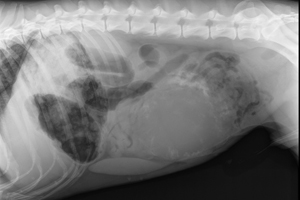

Can you solve this puzzle?

Test your veterinary knowledge with this month’s ‘Brain Teaser,’ featuring a seven-year-old male, intact Belgian Malinois presenting with diarrhea and abdominal discomfort.